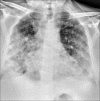

Background: Chest radiography (CXR) is a widely available baseline radiological modality in evaluating symptomatic patients with suspected or confirmed Covid-19 disease. Serial changes can help in monitoring the patients in conjunction with the clinical status of these patients in a hospital setting.

Purpose: The purpose of this study was to analyse the patterns of radiological findings on chest radiograph (CXR) for suspected and confirmed COVID-19 patients on initial presentation to the emergency medical services (EMS) on admission and to assess the progression and resolution.

Results: 756 RT-PCR confirmed COVID-19 patients were included in our study who had initial CXR. 510 (67.46%) of our patients with positive initial RT-PCR showed abnormal baseline CXR. The abnormal findings were described as haziness akin to ground glass opacities (GGO) on CT, peripheral opacities, patchy parenchymal opacities and consolidation. Peripheral opacities and lower zone distribution were the commonest pattern of CXR abnormalities with bilateral involvement. The severity of findings on serial CXR and radiographic regression was studied along with follow-up to assess response to treatment. Forty-six patients showed features of acute lung injury (ALI). Complications and new CXR findings were reported for patients who were given ventilator support.

Conclusion: CXR is a valuable baseline radiological investigation on hospital admission in symptomatic patients with suspected or confirmed Covid-19 presenting to the EMS as it helps to monitor the progress and regression of the disease in conjunction with clinical findings.